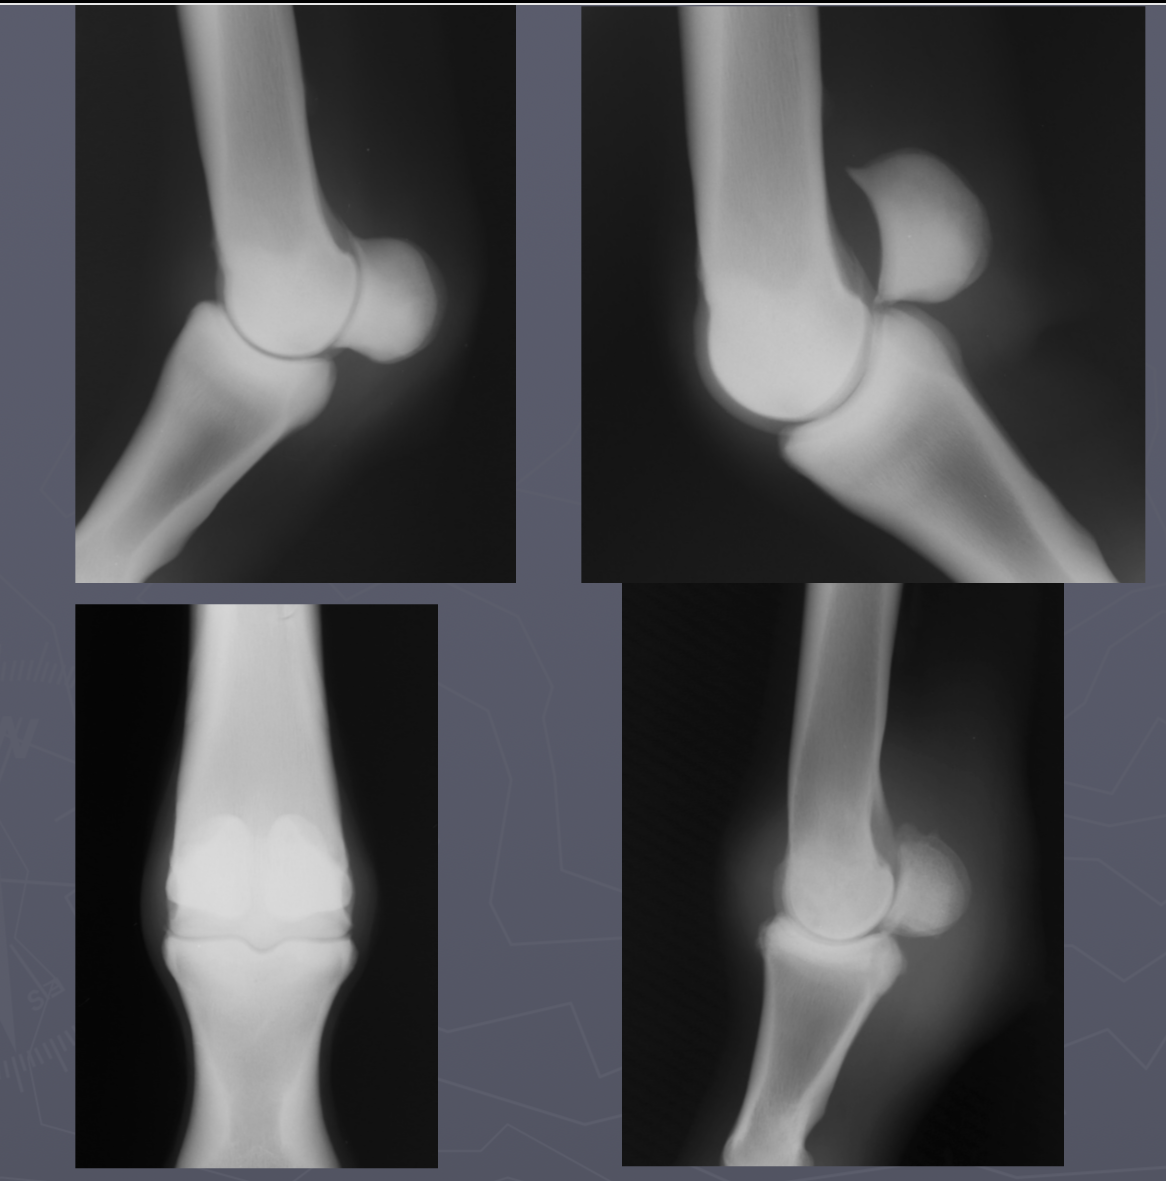

which OCD lesions are these in the dog

A = cd humerus

B = medial humeral condyle (elbow)

C = medial trochlear ridge (ankle)

D =lateral femoral condyle (knee)

Dog OCD signalment

young giant breed (6-9 mo age)